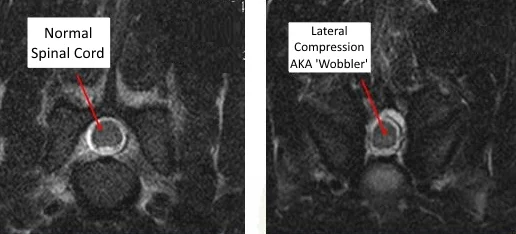

The medical term for the condition in younger dogs is Caudal Cervical Spondylomyelopathy. In this disease, the spinal cord is compressed by increased thickness of the bones in the vertebrae themselves. Typically, this is towards the base of the neck, and it is slowly progressive. While low doses of steroids can help control the disease; this type of medical management does not address the underlying cause and the signs often progress in spite of the drugs. Surgery to remove the compressive bone is often curative but is a complicated procedure and carries some degree of risk.

In older dogs, Wobbler's disease is more aptly termed Disc Associated Wobbler's Syndrome, or DAWS. In these patients the spinal cord compression is caused by bulging of the intervertebral disc and thickening of other supportive ligaments in the vertebrae at the base of the neck. Medical management for this condition also makes use of low-dose steroids. Just like the condition in younger dogs though, medications do not treat the underlying cause and the clinical signs often progress. Surgical options exist for these pets as well, but have often been plagued with complications. Particularly, a problem known as the 'Domino Effect'. We'll discuss this condition and the surgical options in more detail in a later post.